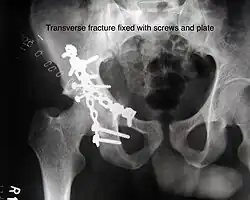

Transverse In this variety of fracture, the innominate bone is broken such that the upper part consists of ilium with weight bearing dome and the lower part consists of ischium and pubic bones. It typically occurs when the injuring force is applied from the side, against the greater trochanter of the femur bone, as in a fall on the side or being hit on the side. This is a two part fracture, but though both columns are broken, it is not a true both-column fracture, as the weight bearing dome is still attached to main ilium.

Depending on the level at which the fracture line passes in relation to weight bearing area, the transverse fracture is further subdivided into types:

1. Infra tectal: below the weight bearing dome

2. Juxta tectal: just at the level of the weight bearing dome

3. Trans tectal: passing through the weight bearing dome

The final management depends on the size of the fragment(s), stability and congruence of the joint. In some cases traction for six to eight weeks may be the only treatment required; however, surgical fixation using screw(s) and plate(s) may be required if the injury is more complex. The latter treatment will be called for if bone fragments do not fall into place, or if they are found in the joint, or if the joint itself is unstable.